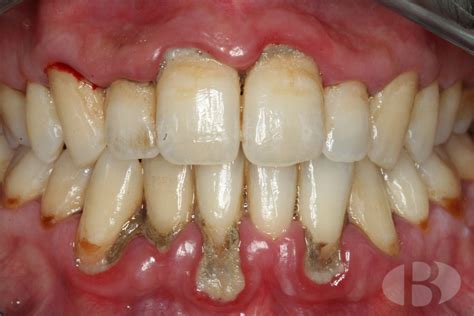

Se presenta al Servicio de Implantología paciente femenino de 25 años de edad, que refiere como antecedentes personales patológicos padecer diabetes mellitus tipo 2 desde hace tres años controlada con metformina. A la exploración bucal se observa un maxilar parcialmente edéntulo, presenta migración patológica generalizada, con depósitos de cálculo, exudado purulento, evidente inflamación gingival, movilidad dental grado II y III; durante el sondeo periodontal presenta pérdida de inserción mayor a 5mm.

Radiográficamente presenta resorción ósea severa, con defectos óseos múltiples. Con base en lo anterior se diagnosticó a la paciente con una periodontitis agresiva generalizada severa asociada a diabetes mellitus con un pronóstico desfavorable para todos los dientes.